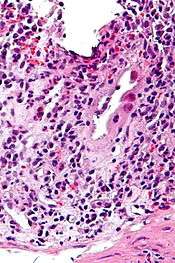

| Micrograph of CMV colitis. H&E stain. | |